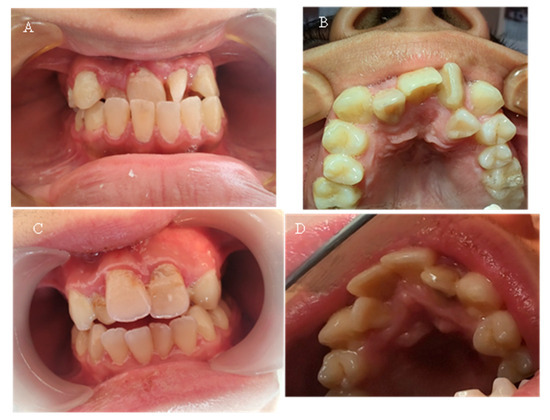

Seven of the eleven examined children were diagnosed with various types of orthodontic deformities: tooth rotations and crowding, open bite, deep bite, overjet, and crossbite in the lateral area (Figure 5). The malocclusions described in the literature, which have a probable relationship with hypophosphatemia—maxillary retrognathia and crowding in the front—were found in only two of the examined children (18.18%).

Figure 5. (A) Case 7—15-year-old—picture of anterior teeth in occlusion; (B) same patient—upper dental arch, occlusal picture; (C) Case 8—15-year-old—anterior teeth in occlusion; (D) same patient—upper dental arch, occlusal picture.

Table 5 presents the malocclusions observed in eleven children with X-linked hypophosphatemic rickets. The table details the specific types of malocclusions for each case, including overjet, open bite, maxillary retrognathia, retrusion in the front, deep bite, crossbite, crowding, and tooth rotations and crowding. Seven of the eleven children (63.64%) exhibited malocclusions, with maxillary retrognathia and retrusion in the front observed in two children (18.18%).